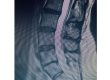

At Texas NeuroSpine Surgery, our goal is to always find the least invasive approaches for the best surgical outcome. However, some cases require more extensive approaches, as in this case of an L4-5 deformity in a patient with rheumatoid arthritis and years of debilitating low back pain. A “front-back” or “anterior-posterior” surgery was needed to correct her deformity and stabilize her spine.